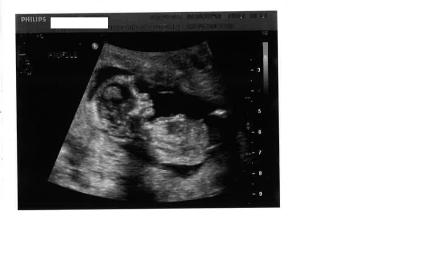

These were taken at 13w3D

Update ** I am adding one more pic if that helps

Attachment 8855Attachment 8856

Is there any nub? what about skull theory?

I'm guessing girl

BOY!

I don't see any clues.

i dont see clues sorry

not sure I see any clues.

Maybe boy?